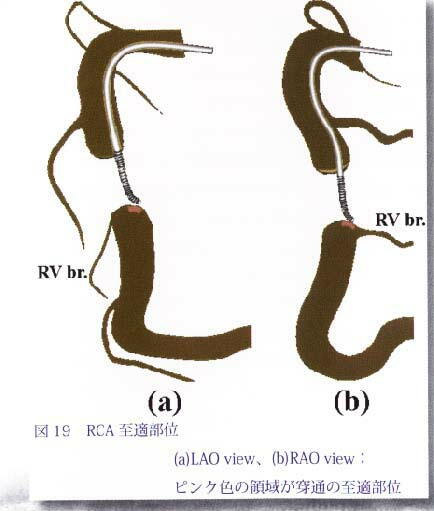

�摜17�F�K�C�h���C���[�͒��u�}�ɓ����Ă���DD1�Ɣ��Α���notch�����肻���D����